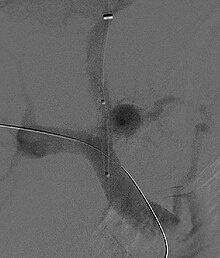

Fluoroscopic image of transjugular intrahepatic portosystemic shunt (TIPS)

Selective shunts select non-intestinal flow to be shunted to the systemic venous drainage while leaving the intestinal venous drainage to continue to pass through the liver. The most well known of this type is the splenorenal.[16] This connects the splenic vein to the left renal vein thus reducing portal system pressure while minimizing any encephalopathy. In an H-shunt, which could be mesocaval (from the superior mesenteric vein to the inferior vena cava) or could be, portocaval (from the portal vein to the inferior vena cava) a graft, either synthetic or the preferred vein harvested from elsewhere on the patient's body, is connected between the superior mesenteric vein and the inferior vena cava. The size of this shunt will determine how selective it is.[17][18]

With the advent of transjugular intrahepatic portosystemic shunting (TIPS), portosystemic shunts are less performed. TIPS has the advantage of being easier to perform and doesn't disrupt the liver's vascularity.[19]